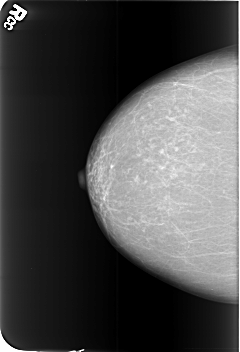

B_3442_1.RIGHT_MLO

B_3442_1.RIGHT_CC

RIGHT_CC LINES 5632 PIXELS_PER_LINE 3832 BITS_PER_PIXEL 12 RESOLUTION 50 NON_OVERLAY